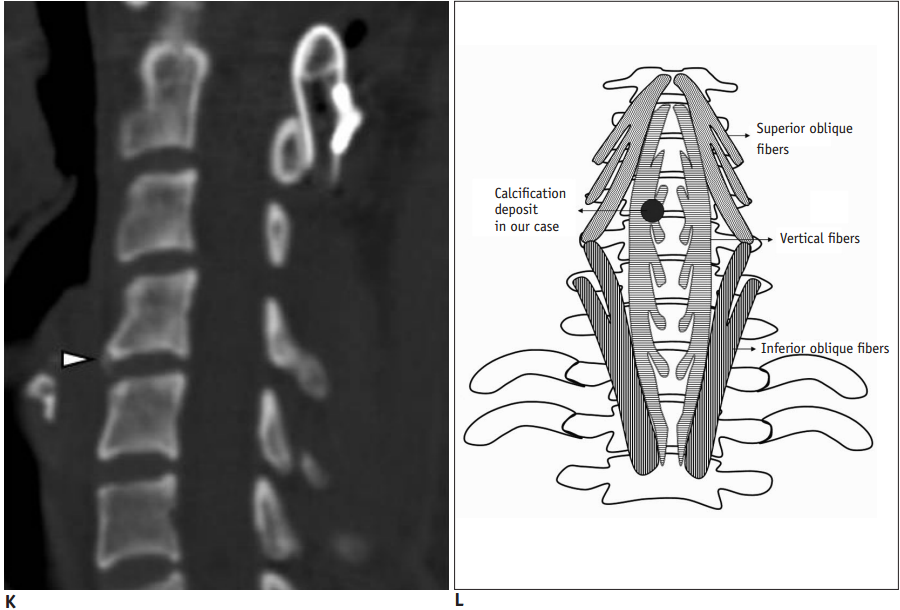

30岁女性,诊断为颈长肌钙化性肌腱炎,但钙化位于不寻常的位置:C4-5椎间隙前侧。A:颈椎侧位片示寰枢椎半脱位(长箭头)和椎前软组织肿胀(无线箭头);B,C和D:颈椎MRI示C1-6椎前软组织肿胀伴积液,D示齿状突骨侵蚀(无线箭头)

上述病人,E为增强,F为抑制像,G和H:经非甾体抗炎药治疗3天后查颈椎CT示C4-5椎前无定形钙化。

上述病人,I和J: 入院4天后复查颈椎MRI示椎前积液明显减少; K,随访2个月复查CT示C4-5前钙化灶减小。(PMID: 21852912)